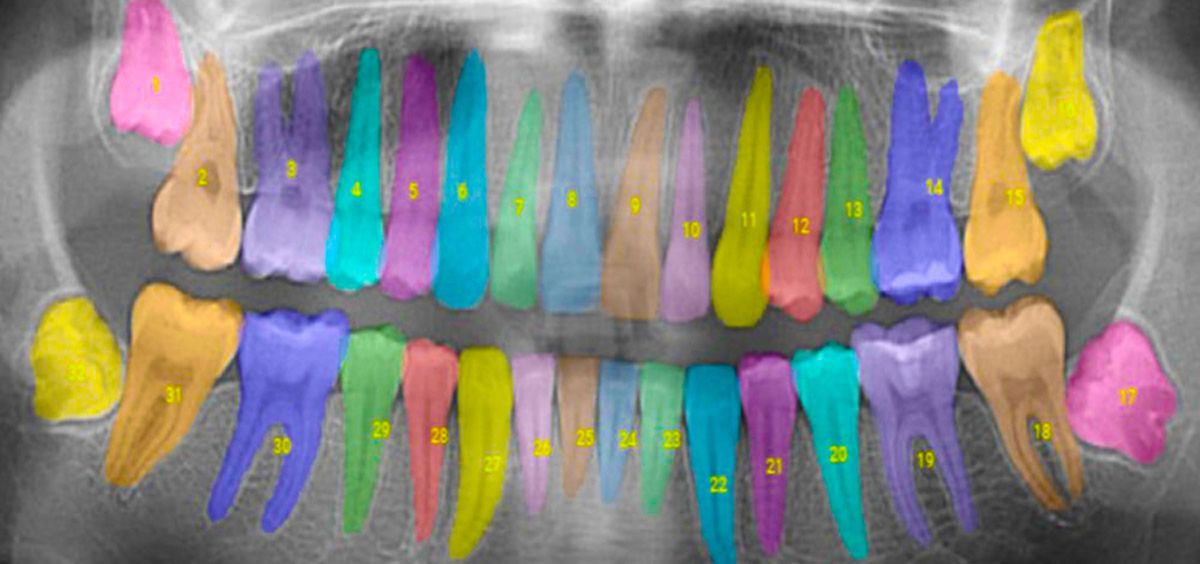

El software proporciona información sobre el tipo de radiografía tomada, cómo se puede impactar un diente, el nivel exacto de pérdida ósea con superposiciones de color, así como la ubicación y la gravedad de las caries

Cuando se importa una radiografía dental a una computadora, el software de Overjet analiza las imágenes automáticamente. Cuando la imagen aparece en la pantalla de la computadora tiene información sobre el tipo de radiografía tomada, cómo se puede impactar un diente, el nivel exacto de pérdida ósea con superposiciones de color, así como la ubicación y la gravedad de las caries.

Overjet también incorpora información histórica sobre cada paciente, rastreando la pérdida ósea en cada diente y ayudando a los dentistas a detectar casos en los que la enfermedad progresa más rápidamente.